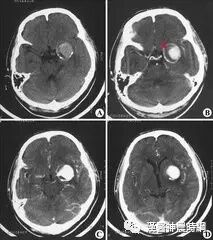

未破裂动脉瘤有局部症状或颅内压增高表现者,以及破裂出血引起蛛网膜下腔出血者尚需要与颅内肿瘤,脑血管畸形,高血压性脑出血,烟雾病,颅脑损伤,血液病,脊髓血管畸形等疾病相鉴别。

1.颅内肿瘤 鞍上区动脉瘤常误诊为鞍区肿瘤,但鞍上区动脉瘤没有蝶鞍的球形扩大,缺乏垂体功能低下的表现,颅内肿瘤卒中出血多见于各种胶质瘤,转移瘤,脑膜瘤,垂体瘤,脉络丛乳头状瘤等,在出血前多有颅内压增高及病灶定位体征,无再出血现象,据CT扫描及脑血管造影可容易鉴别。